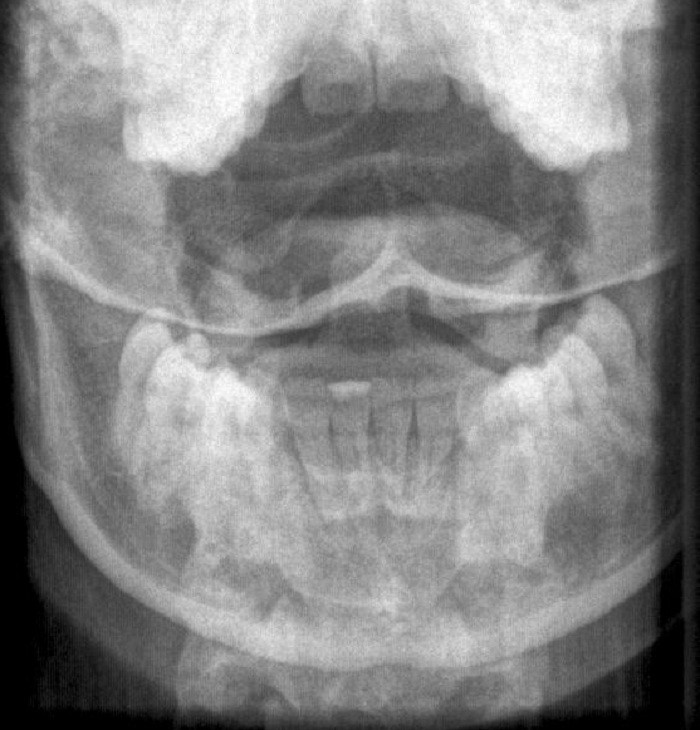

Kriterien für Instabilität (Konsequenz: Operation) an unterer BWS und LWS anhand 3-Säulen Modells von Denis

- Vordere Säule (A): vorderes Längsband, vordere 2/3 des Wirbelkörpers und Diskus

- Mittlere Säule (B): Hinteres Längsband, hinteres 1/3 des Wirbelkörpers und Diskus

- Hintere Säule (C): Wirbelbogen, Ligg. interspinosa et flave, Kapseln der Intervertebralgelenke

3-SäulenModell von Denis

Gemäß dieses Models gelten Verletzungen einer Säule als stabil, Verletzungen von zwei oder drei Säulen als instabil. Bei der Beteiligung der mittleren Säule muss immer von Instabilität ausgegangen werden.